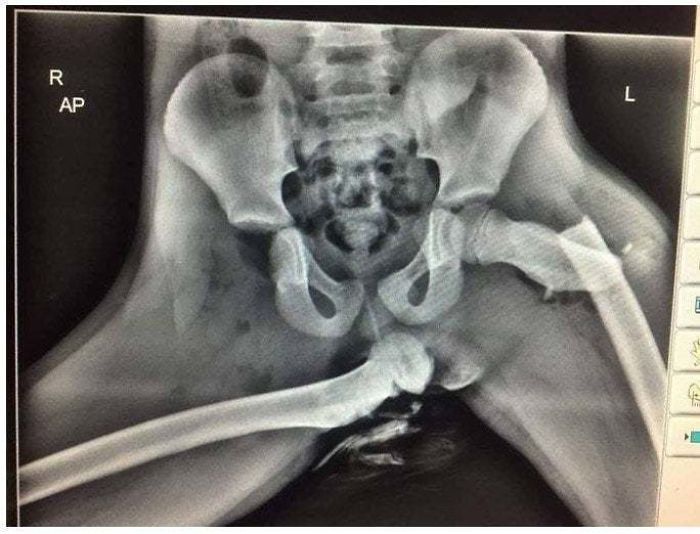

#11 What Could Go Wrong If You Keep Your Feet On The Dashboard And Get Into A Car Crash

Image source: reddit.com